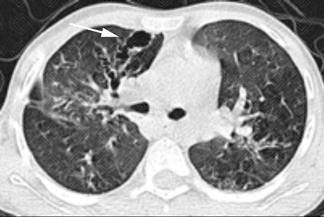

Descrição das imagens: Paciente infantil, sexo masculino, 11 anos, em acompanhamento de fibrose cística. Na tomografia de tórax observam-se extensas bronquiectasias varicosas (setas brancas).

• Tomografia computadorizada do tórax: D etecta-se bronquiectasia quando o diâmetro interno do brônquio aparece maior que o diâmetro do vaso pulmonar adjacente (artéria), descrito com sinal do anel em sinete (primeira imagem).

3. Varicosas: Os brônquios dilatados não possuem tamanho ou forma regulares, apresentando várias áreas de constrições.